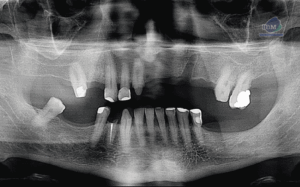

Paciente femenino de 87 años de edad, es referido al Instituto de Diagnóstico Maxilofacial – IDM para evaluación general.En la radiografía panorámica (Figura 1), se